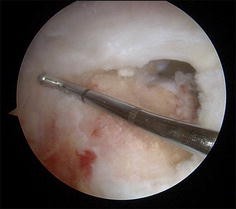

Fig. 1